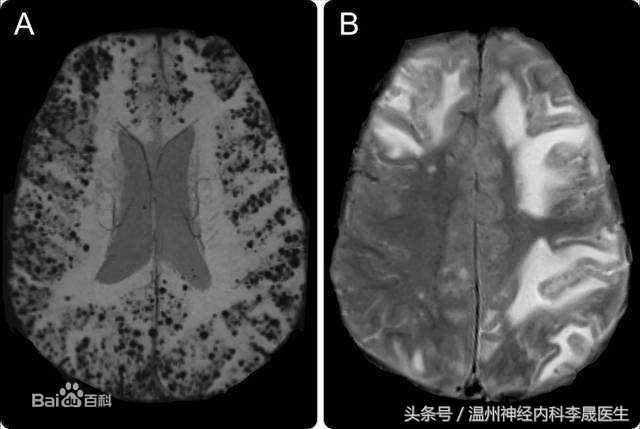

壳核出血

壳核出血(大)

壳核出血(A)小壳核范围内的出血,(B)侵犯了内囊,(C)血肿压迫侧脑室

轴位脑切面示意图,(1)前部型累及壳核前部和内囊前肢;(2)中间型包括内囊膝,苍白球和壳核的中间部分(3)后部型累及内囊后肢远端且常累及是辐射并向颞叶蔓延